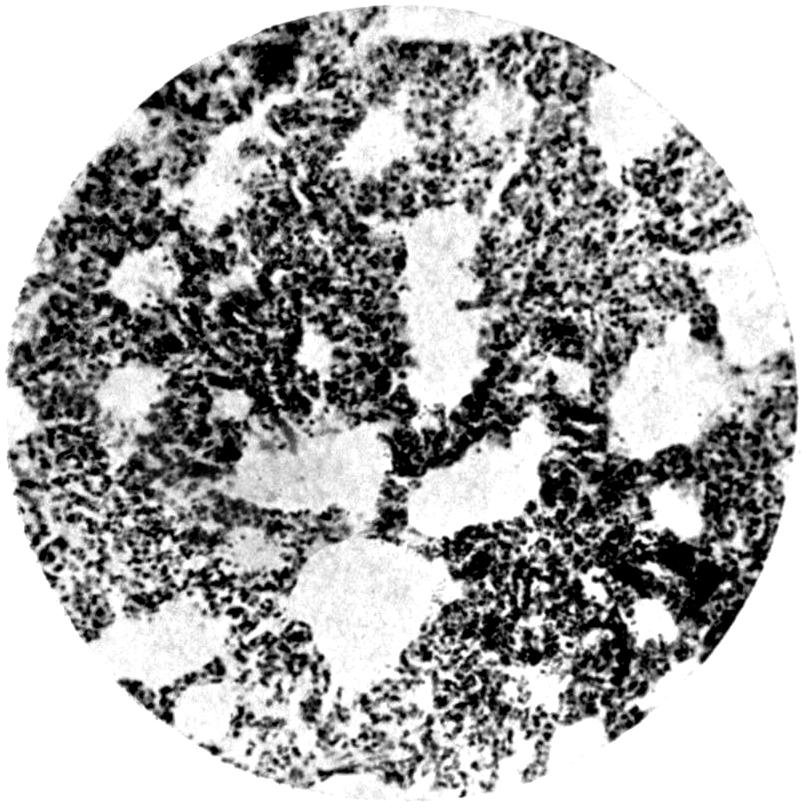

Plate III. 95